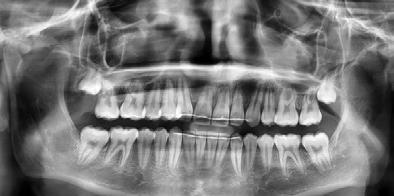

Estudios radiográficos de inicio

Al análisis radiográfico (Figura 3) se observa la clase II esquelética, patrón de crecimiento normodivergente, incisivo superior con adecuada inclinación respecto a su base ósea, incisivo inferior ligeramente proinclinado y vías aéreas permeables. En la radiografía panorámica (Figura 4) se ven 33 órganos dentarios OD, el infantil 53 presente en boca, el OD 13 impactado, los 37 y 47 en proceso de erupción y los terceros molares en formación.

En los cortes tomográficos, en el corte coronal (Figura 5) se muestra el OD 13 impactado y su proximidad con el incisivo lateral, en el corte sagital (Figura 6) grado de reabsorción radicular del OD 12.